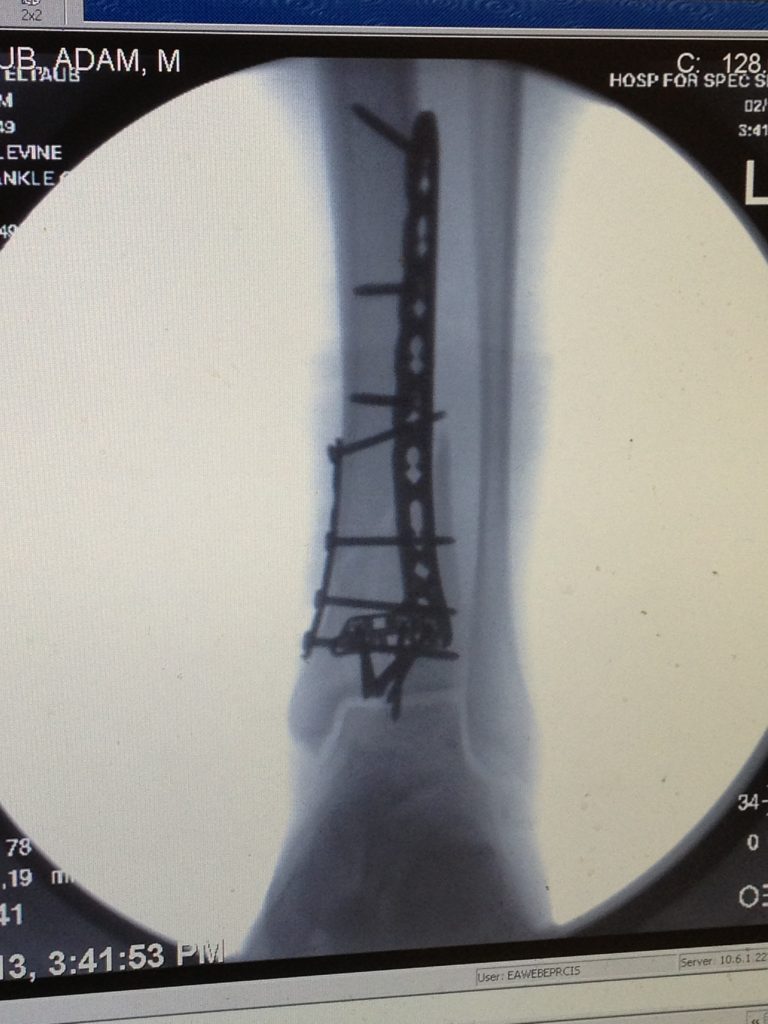

The next morning I was in Dr. Levine's office and the x-ray and MRI confirmed that I had indeed shattered my tibia into multiple pieces (x-ray and MRI attached). Surgery was scheduled for 3 days later on Valentine's Day 2013. The surgery lasted just shy of 6 hours as Dr. Levine pieced my leg together with multiple plates and a more than a dozen screws (post-surgery x-ray attached). The anesthesiologists (Drs. Michael Gordon, James Beckman, and Seth Waldman), Dr. Levine's PA, Lisa Pearson, and the entire staff were fabulous.

Needless to say, I made a full recovery and I am able to fully enjoy the outdoors again. Every time I look at the post-surgery x-ray, I am in awe that Dr. Levine was able to put all the pieces together - that I am back to aggressive skiing and kitesurfing with no limitations whatsoever. Some of my most meaningful family time is spent on the ski slopes with my wife and two daughters and will forever be grateful to Dr. Levine for getting me Back in the Game.